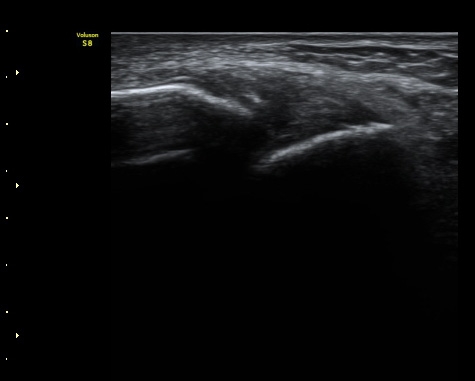

3ÁÖ ÈÄ ÃßÀû°Ë»ç¿¡¼­ ¹Ú¸®µÈ°ñÆíÀÌ °üÂûµÇ°í ÀδëÀÇ Àú¿¡ÄÚ ºÎÁ¾Àº ¾à°£

Áõ°¡µÈ ¼Ò°ßÀ» º¸ÀÓ(±×¸² 3, 4).